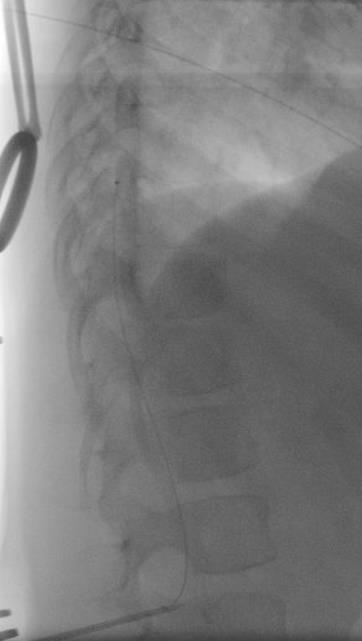

SDR involves surgically accessing the spinal cord (typically in the lumbosacral region, L2 to S1 or S2).The dorsal (sensory) nerve roots are carefully identified and then divided into smaller bundles called rootlets.